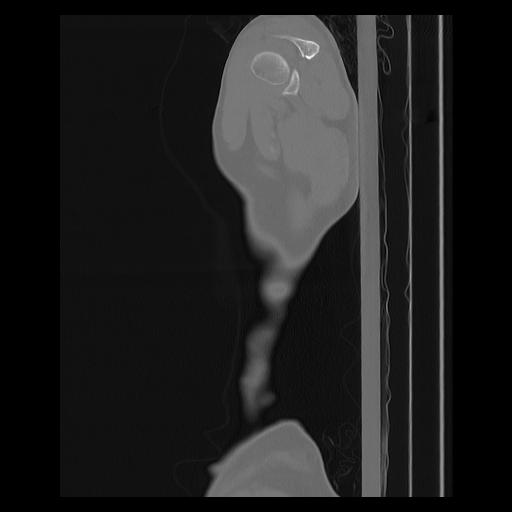

33 PULMON,CE,Sagittal,3.000,PULMON,Sagittal,